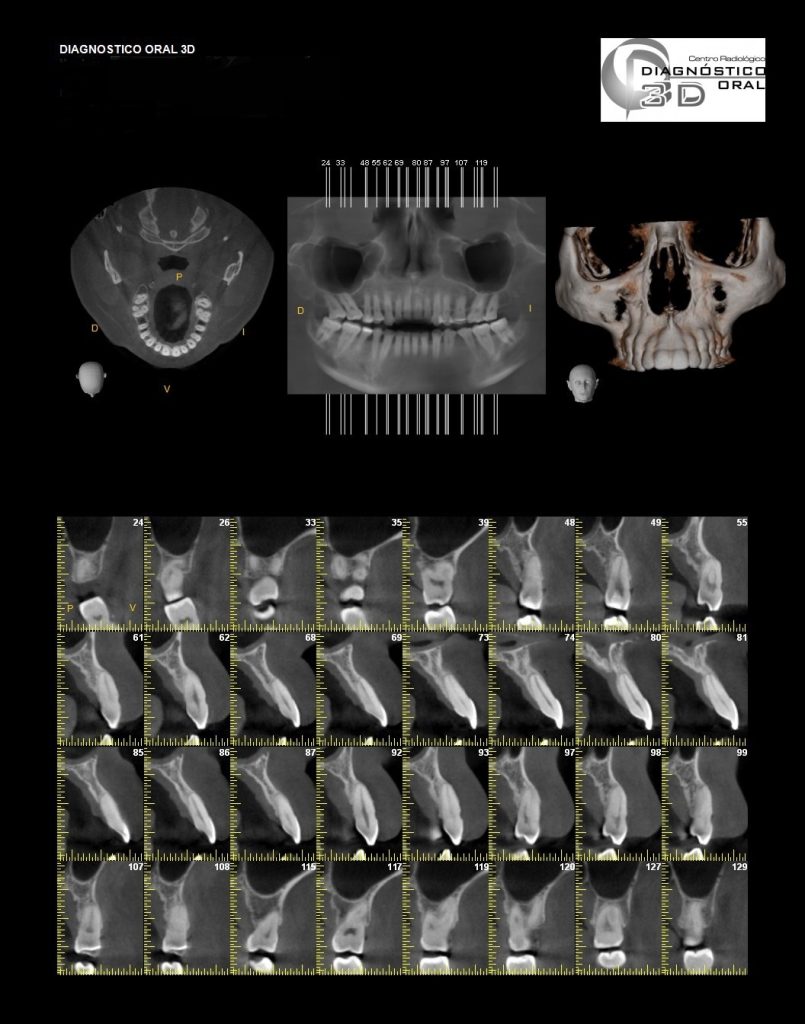

El Centro Radiológico Diagnóstico Oral 3D, es una empresa antioqueña que ofrece a sus pacientes desde el año 2009, tecnología de vanguardia en radiografías tridimensionales con calidad fotográfica. Las posibilidades para mejorar la eficacia en los diagnósticos bucales son evidentes, también lo son las posibilidades de manipulación de imagen. El sistema de imágenes en 3D ofrece detalles sin precedentes, convirtiéndola en la opción idónea para la mayoría de aplicaciones odontológicas, incluyendo implantes, tratamiento de conductos, ortodoncia, odontopediatría, periodoncia y cirugía

El mayor beneficiado con el uso de esta tecnología es el paciente, el cual podrá ser evaluado en todas sus dimensiones con una baja dosis de radiación, con un costo accesible y sin contaminar  el medio ambiente. Dependiendo de la necesidad del paciente, hay varios tipos de tomografías y los especialistas en el área odontológica hacen uso de ellas según su especialidad.

Evaluación de patologías dentales y maxilofaciales

Planificación de tratamientos ortodónticos y ortognáticos

Implantología dental